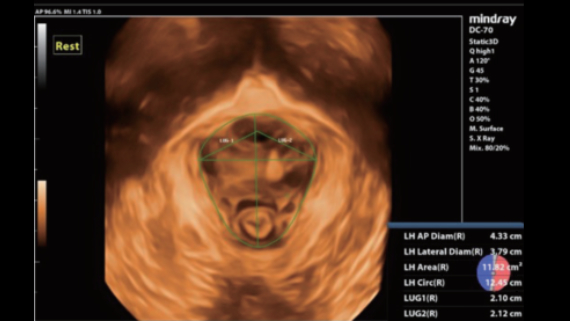

–°–Њ–≤–Љ–µ—Б—В–љ–Њ —Б —Б–Њ–≤—А–µ–Љ–µ–љ–љ—Л–Љ–Є —Г–ї—М—В—А–∞–Ј–≤—Г–Ї–Њ–≤—Л–Љ–Є —В–µ—Е–љ–Њ–ї–Њ–≥–Є—П–Љ–Є –љ–Њ–≤–Њ–µ —А–µ—И–µ–љ–Є–µ –Њ—В Mindray –њ—А–µ–Њ–±—А–∞–Ј—Г–µ—В –∞–Ї—В—Г–∞–ї—М–љ—Л–µ –Ј–∞–і–∞—З–Є –Ї–ї–Є–µ–љ—В–Њ–≤ –≤ –Ї–ї–Є–љ–Є—З–µ—Б–Ї–Є–µ –њ–Њ—В—А–µ–±–љ–Њ—Б—В–Є.

–°–Є—Б—В–µ–Љ–∞ DC-70 Exp —Б X-Insight –њ–Њ–Љ–Њ–≥–∞–µ—В —Г–њ—А–∞–≤–ї—П—В—М –њ–Њ–≤—Б–µ–і–љ–µ–≤–љ–Њ–є –Ї–ї–Є–љ–Є—З–µ—Б–Ї–Њ–є –њ—А–∞–Ї—В–Є–Ї–Њ–є —Б –ї–µ–≥–Ї–Њ—Б—В—М—О –Є —Г–≤–µ—А–µ–љ–љ–Њ—Б—В—М—О.

–Ю—Б–љ–Њ–≤—Л–≤–∞—П—Б—М –љ–∞ –≥–ї—Г–±–Њ–Ї–Њ–Љ –њ–Њ–љ–Є–Љ–∞–љ–Є–Є –њ–Њ—В—А–µ–±–љ–Њ—Б—В–µ–є –Ї–ї–Є–µ–љ—В–Њ–≤, –Ї–Њ–Љ–њ–∞–љ–Є—П Mindray —А–∞–Ј—А–∞–±–Њ—В–∞–ї–∞ —Б–Є—Б—В–µ–Љ—Г DC-70 Exp —Б X-Insight, —З—В–Њ–±—Л –Њ–±–µ—Б–њ–µ—З–Є—В—М eXpress Clarity, eXceptional Intelligence, eXceeding Experience.